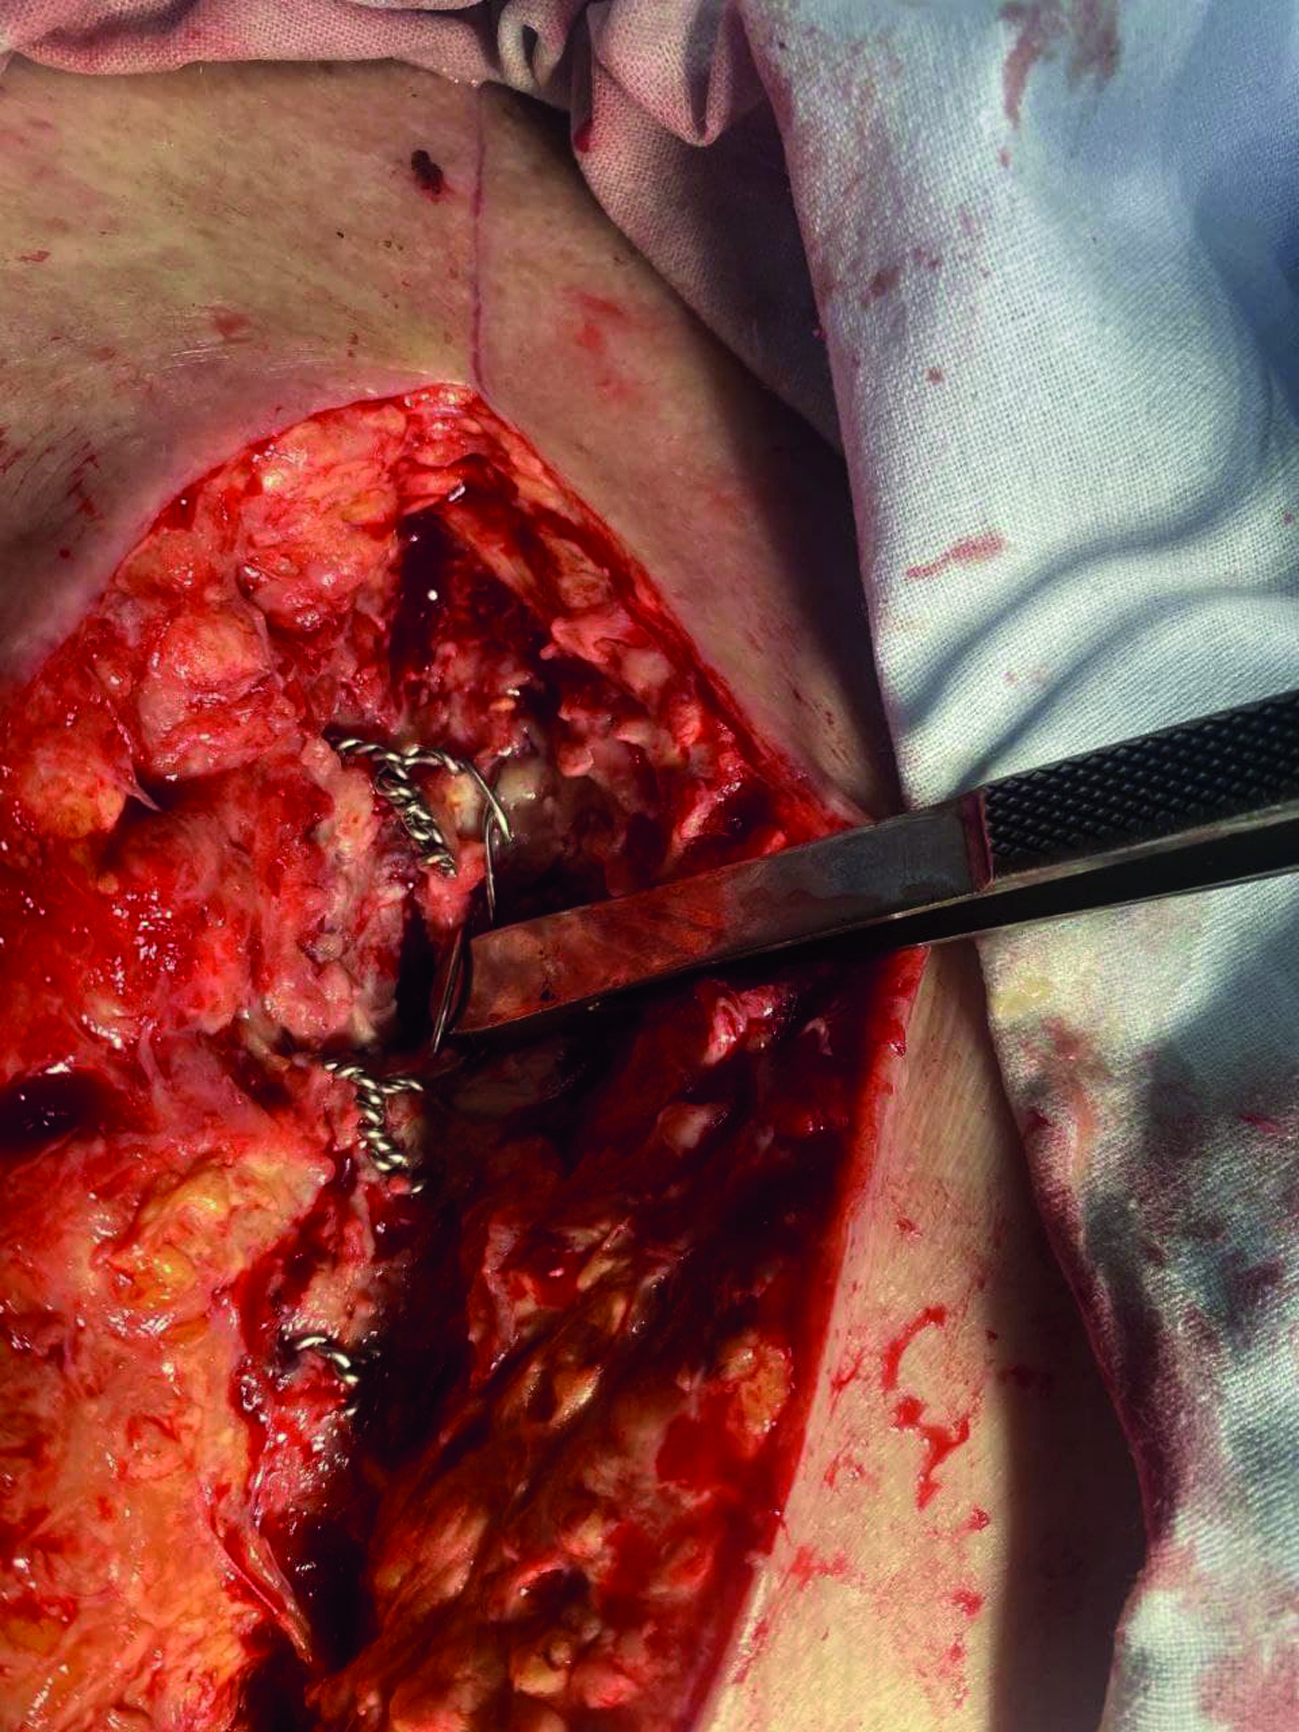

Рисунок 3. Интраоперационное фото. Деструкция грудины в зоне металлических лигатур.

Figure 3. Intraoperative photo. Destruction of the sternum in the area of metal ligatures.